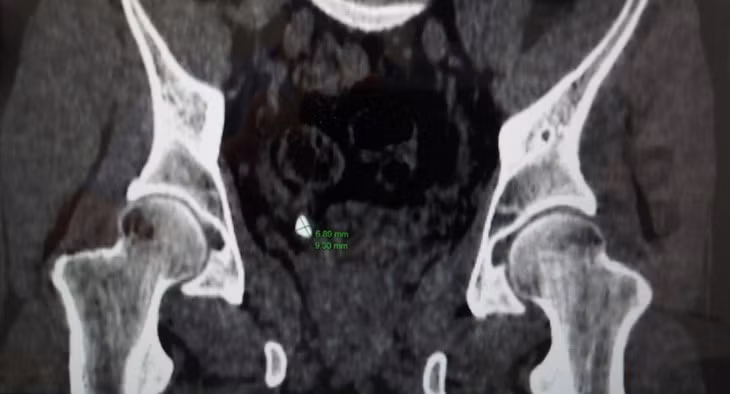

Ngay lập tức, người bệnh được các bác sĩ chỉ định làm các xét nghiệm, siêu âm bụng, chụp cắt lớp vi tính và xác định người bệnh bị sỏi niệu quản phải 1/3 dưới (nằm ở vị trí đoạn nối của niệu quản khi vào tới bàng quang), sỏi kích thước xấp xỉ 9x7mm.

Hình ảnh thận của bệnh nhân trên phim chụp - Ảnh: BVCC

Bất ngờ hơn, kết quả chụp CT các bác sĩ phát hiện người bệnh có thận niệu quản đôi hoàn toàn hai bên trái, phải và hai niệu quản riêng biệt đều cắm xuống bàng quang. Người bệnh có bất thường về giải phẫu hệ tiết niệu, có nhiều đơn vị thận hơn bình thường là một trong những nguyên nhân hình thành sỏi thận.